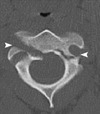

Agenesia completa del arco posterior del atlas

- Variante

- Se ve en la Rx lateral y, mejor, en la TAC

- Diferenciar de: occipitalización del atlas, destrucción ósea (metástasis, quiste óseo aneurismático, osteoblastoma… ), fractura

Agenesia parcial del arco posterior del atlas

- Variante

- Se ve en la Rx lateral y, mejor, en la TAC

- Diferenciar de: occipitalización del atlas, destrucción ósea (metástasis, quiste óseo aneurismático, osteoblastoma… ), fractura